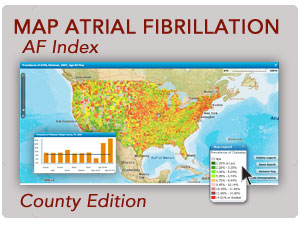

New Results From the National Health and Wellness Survey Show Patients at High Risk for Stroke Have Lower Quality of Life, More Hospitalizations NEW YORK, NY, Nov 07, 2011 (MARKETWIRE via COMTEX) — Nearly 40% of diagnosed “high-risk” atrial fibrillation (AF) patients in the 5EU are not taking an anticoagulant to prevent stroke, according to […]